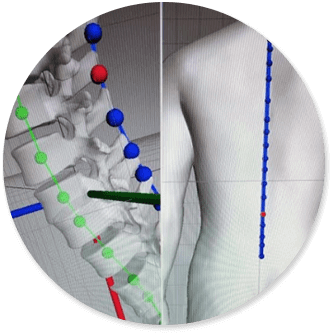

Оптическая диагностика позвоночника Diers: изображения и технологии